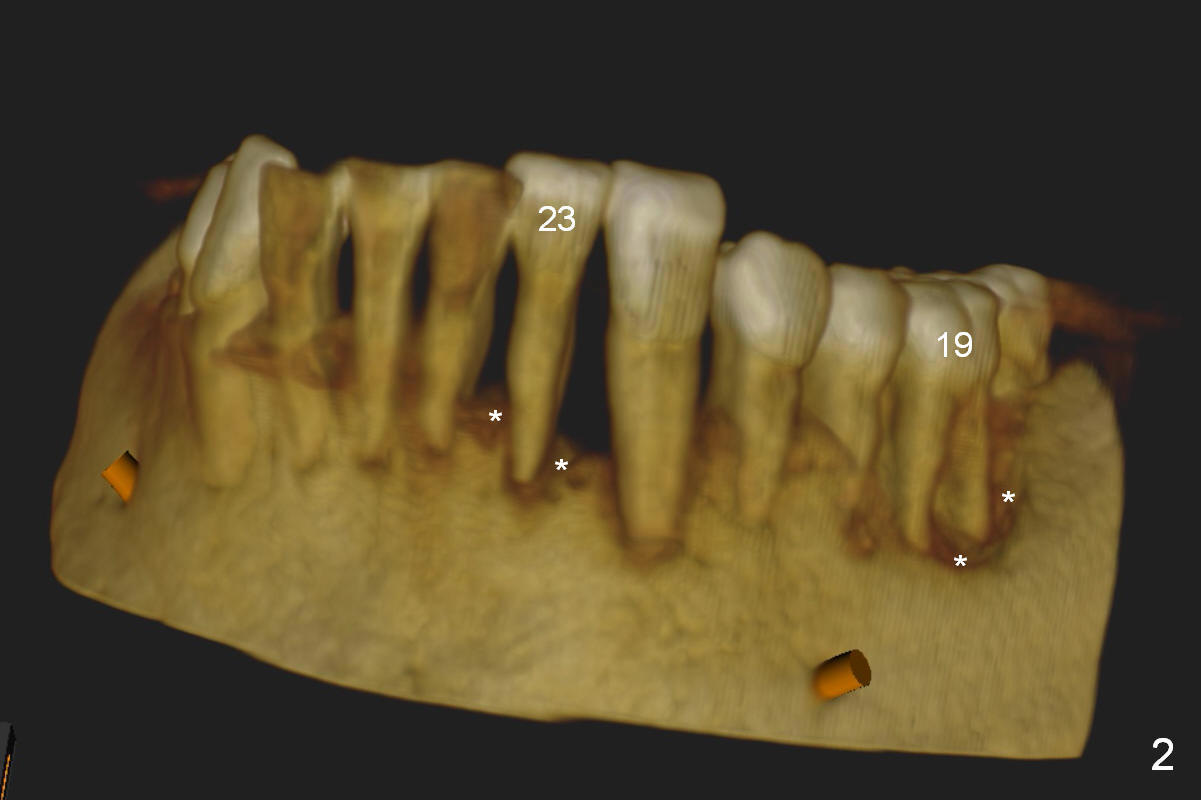

A 45-year-old man (SH) has periodontal (#3,9,19,23 (bone loss: Fig.1-3 *)) and orthodontic (#7,10 cross bite) problems, which he wants to solve at the same times. The tooth #19 is symptomatic (Fig.4,5). Infiltrate the buccal plate with 2% Xylocaine 1:50,000 Epinephrine and Septocaine (away from the Mental Foramen). After extraction and debridement, the socket is treated with Metronidazole. Osteotomy is initiated slightly buccal (B) to the middle of the socket bottom (Fig.5), using Sinus Master Kit drills (6 mm deep). After each drill, gently explore the lingual wall of the osteotomy with a fine curette or an explorer to determine whether the wall is perforated or not. Place a 5.5x13 mm implant (or short) between the buccal plate and the Inferior Alveolar Nerve (brown circle). If the torque is high, use the corresponding drill and tap. A 5.5 mm angled abutment will be used (15 or 25°, will arrive Monday morning). When X-ray is taken, the apex of the osteotomy should be superior to the upper border of the Inferior Alveolar Canal (Fig.4 U) and inferior to the Lower one (L). Bone graft is placed (Fig.4,5 red circles) after placement of PRF buccally (Fig.5 yellow curved line). If visibility is poor, make an incision and insert Epinephrine gauze under periosteum for hemostasis. Take photos when a 2 mm pilot drill in place to show the coronal end of the drill at the lingual cusp instead of the central fossa.